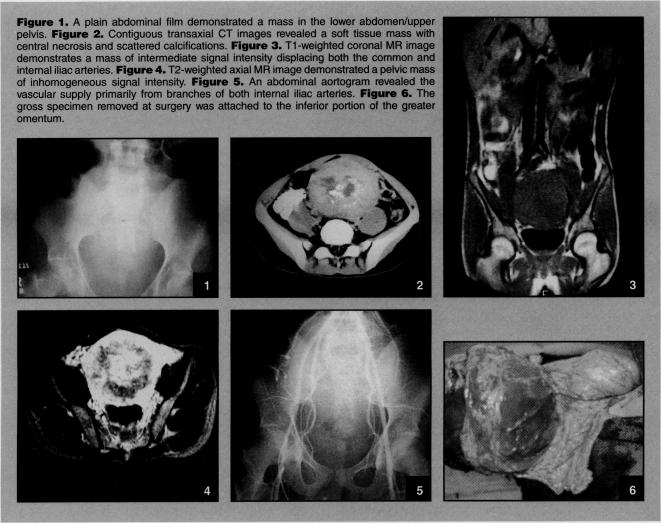

腹部非典型硬纤维瘤:1例病例报告

Desmoids are rare lesions that are histologically benign but locally aggressive. These lesions should be considered in patients who present with abdominal masses, particularly if there is a prior history of familial polyposis. This case report describes a patient with an abdominal desmoid that demonstrated atypical features on computed tomography and correlative magnetic resonance images.

硬纤维瘤是一种罕见的病变,组织学上为良性,但具有局部侵袭性。对于出现腹部肿块的患者,尤其是有家族性息肉病既往史的患者,应考虑到这些病变。本病例报告描述了一名患有腹部硬纤维瘤的患者,其在计算机断层扫描和相关磁共振图像上表现出非典型特征。